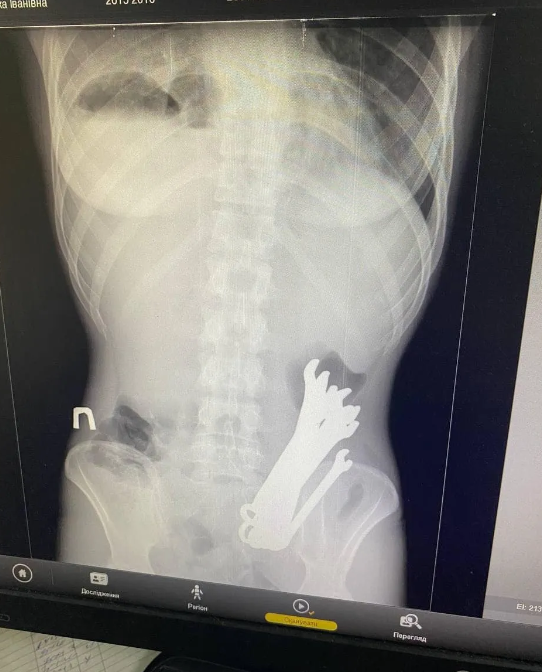

У Черкасах лікарі здійснили надзвичайну операцію, під час якої з шлунку пацієнта було вилучено шість гайкових ключів. Про випадок розповіли на Facebook-сторінці відділення торакальної хірургії Черкаської обласної лікарні.

Чоловіка госпіталізували з серйозними ускладненнями: гнійним запаленням м'яких тканин шиї, розривом стравоходу, медіастинітом (запаленням середостіння) і емпіємою плеври (скупченням гною в грудній порожнині).

Медики провели складну хірургічну операцію, під час якої наклали гастростому для забезпечення відведення вмісту шлунка. Інструменти успішно видалили, і після трьох тижнів лікування пацієнта виписали з лікарні в стані одужання.